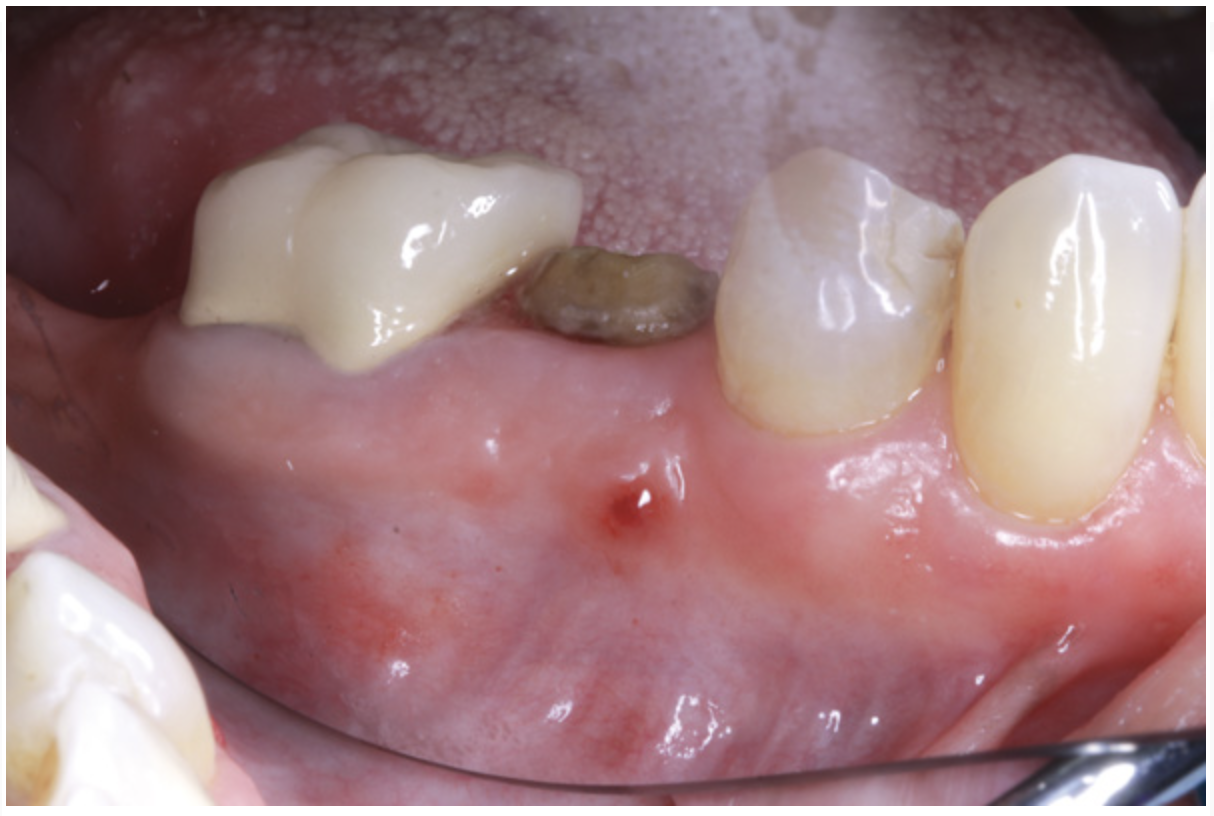

Suppuration is a cardinal sign of an infection, yet it may not be present. Pus is usually a thick viscous fluid that is often created in response to an infection. As the neutrophils die, they are destroyed by macrophages, thereby forming pus. Pus is usually white or yellow, but it can be red, green, or blue (Figure 3 and Figure 4).18 White and yellow pus typically reflect an infection with Streptococcus pyogenes or Staphylococous aureus.19 A red discharge reflects blood mixing with the pus. If the pus is green, it is due to incorporation of myleperoxidase, which is produced by neutrophils.19 A clear fluid (serum) reflects healing and is not considered a sign of an infection.19

Figure 3 Clinical view of site No. 12 demonstrating pus upon palpation. Pus can be different colors. Not all infected sites manifest pus. (Photograph courtesy of Dr. John Cavallaro.)

Figure 3